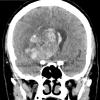

NEOPLASMS (GLIAL)

Glioblastoma, adenoid pattern (7)